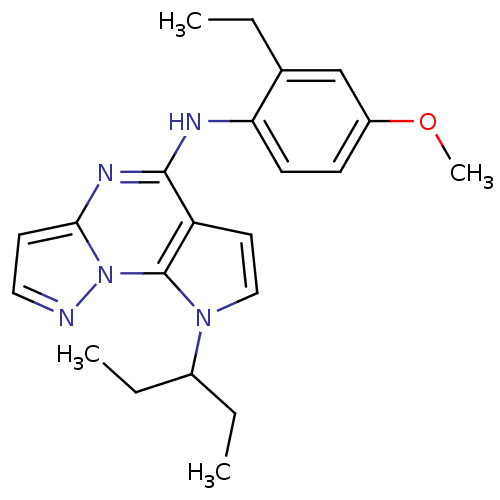

TargetCorticotropin-releasing factor receptor 1(Homo sapiens (Human))

Dupont Pharmaceuticals

Curated by ChEMBL

Dupont Pharmaceuticals

Curated by ChEMBL

Affinity DataEC50: 1.10nMAssay Description:Antagonist activity at human CRFR1 expressed in HEK293 cells assessed as inhibition of sauvagine-induced cAMP accumulation by measuring sauvagine EC5...More data for this Ligand-Target Pair